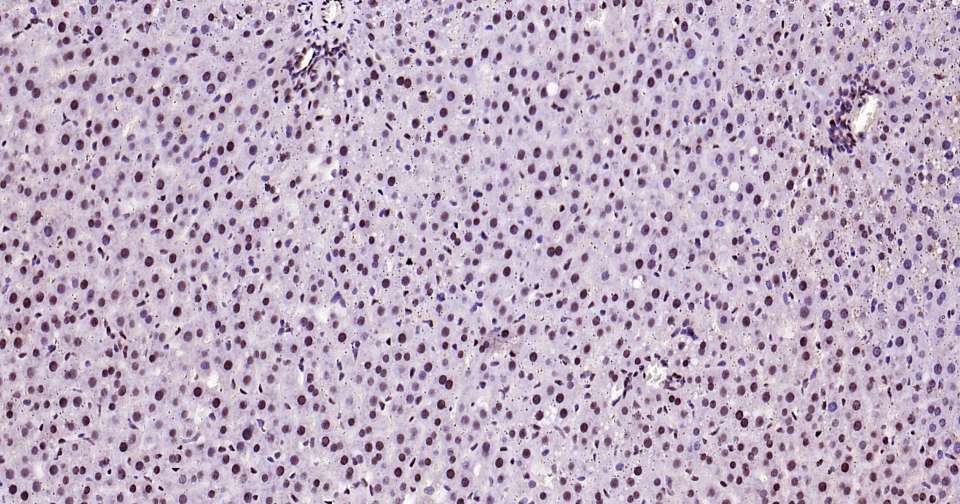

Immunohistochemical analysis of paraffin embedded rat brain tissue slide using IHC0387R (Rat phospho-STAT3 (Ser727) Kit).

Immunohistochemical analysis of paraffin embedded rat liver tissue slide using IHC0387R (Rat phospho-STAT3 (Ser727) Kit).